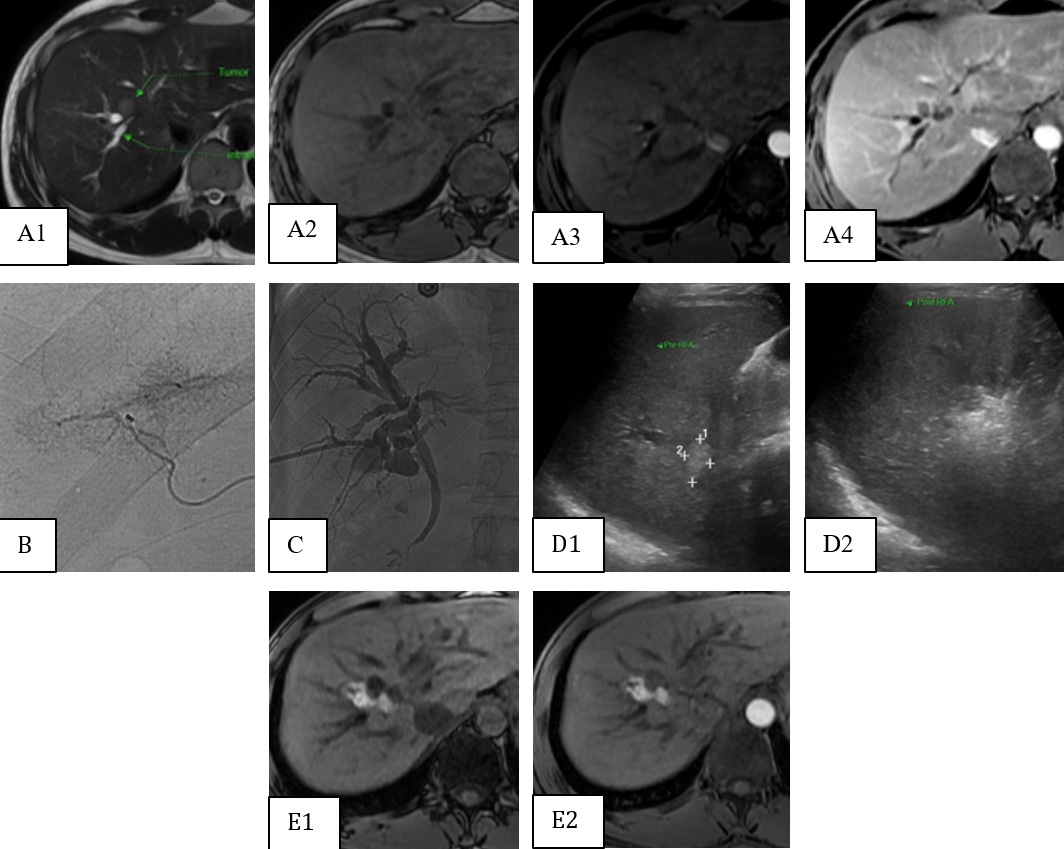

Figure 1 : Homme, 44 ans, hépatite B. Découverte d’une tumeur au foie droite : hypersignal discret en T2 (A1), hyposignal en T1 (A2), hyper-vascularisation en phase artérielle (A3) avec lavage en phase portale (A4). Le patient refuse la chirurgie et TACE non réalisable (B). Mise en place d’un drain biliaire au contact de la tumeur (C), avec infusion biliaire continue et refroidissement pendant la procédure de RFA. L’image d’échographie de tumeur avant (D1) et après la procédure (D2). Ablation complète par RFA sans atteinte des voies biliaires en T1 (E1), absence de rehaussement en phase artérielle (E2).